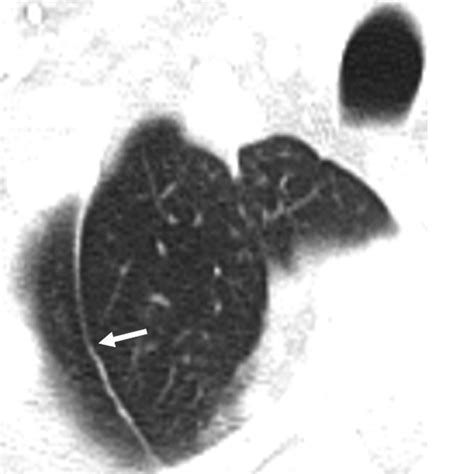

During normal fetal development, the azygos vein arcs over the apex of the right lung to enter the superior vena cava. In individuals who develop an azygos lobe, the vein fails to migrate to its normal position over the apex. Instead, it cuts through the developing upper lobe of the right lung. As it traverses the lung tissue, the vein drags two layers of parietal pleura and two layers of visceral pleura with it, creating a fissure known as the fissura azygos.

• The Azygos Fissure Line: A thin, convex line extending from the apex of the right lung toward the hilum.

While standard chest X-rays are usually sufficient for diagnosis, computed tomography (CT) provides a definitive view. On a CT scan, the Vena Azygos Lobe is clearly demonstrated as an isolated pleural-lined segment of lung tissue separated from the rest of the right upper lobe by the azygos fissure.